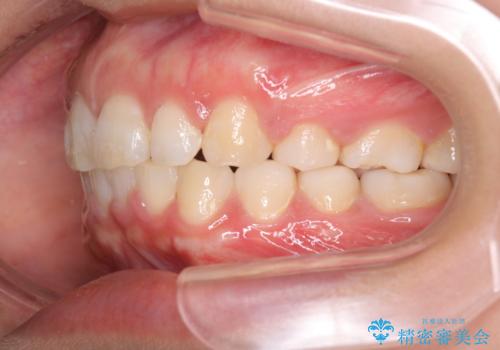

- 出っ歯を主訴に来院されました。

下の歯並びに対して、上の歯が全体的に前方に位置している状態でした。

抜歯をすることでしっかり前歯を後方に移動させて、引っ込めることができました。